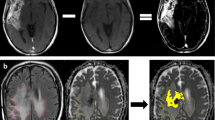

Between November 2019 and August 2020, seven patients (aged 21–75 years at initial diagnosis; two females) with suspicion of recurrent glioblastoma received [68Ga]Ga-Pentixafor PET. Details of these patients can be found in Table 4; representative examples of [68Ga]Ga-Pentixafor PET images in Fig 5. All patients showed low to moderate uptake in the tumor (mean SUVmean 1.45; mean SUVmax 2.06) compared with bloodpool activity (mean SUVmean 1.36). The very low background activity (mean SUVmean 0.03; mean SUVmax 0.10) leads to a relatively high TBR (mean TBRmean 67.0; mean TBRmax 65.6) even with low to moderate uptake.

Axial [68Ga]Ga-Pentixafor PET (A1; B1; C1), T2-weighted MRI (A2; B2; C2) and fused [68Ga]Ga-Pentixafor PET/MRI (A3; B3; C3) images of three patients with suspicion of recurrent glioblastoma. (A) Male (patient no. 4 in Table 4) showing higher uptake (SUVmax 3.5) in the MR-enhancing tissue in the left cerebellar hemisphere compared to the other patients and than bloodpool activity (SUVmean 1.48). (B) Female (patient no. 2) showing low to moderate uptake (SUVmax 1.82) in the MR-enhancing tissue in the left frontal lobe slightly higher than bloodpool activity (SUVmean 1.23). (C) Male (patient no. 6) showing low uptake (SUVmax 1.46) in the MR-enhancing tissue in the left frontal lobe equal to bloodpool activity (SUVmean 1.48)

Comparable to the TMA analysis, all patients showed large intra-tumor variation for CXCR4 staining, even within one section. However, this variation did not fully correspond with the variation of [68Ga]Ga-Pentixafor uptake; for instance, patient no. 3 showed low uptake, but CXCR4 tumor cell staining varying from negative to strong. Only one patient (no. 4) showed higher tumor uptake compared with the other patients that indeed corresponded with locally moderate to strong CXCR4 tumor cell staining; unfortunately, due to a combination of factors there was not enough clinical support to proceed to therapy with [177Lu]Lu-Pentixather. In addition, another patient (no. 5) was CXCR4 negative with a corresponding lower [68Ga]Ga-Pentixafor uptake (Table 4). Interestingly, in one patient (no. 6), a small subset of neurons (with the appearance of “dark neurons”) in tumor-infiltrated cortex also showed strong cytoplasmic CXCR4 staining, while the vast majority of neurons was completely negative (Fig. 6).

Example of intra-tumoral heterogeneity of CXCR4 staining in recurrent glioblastoma tissue of patient no. 6. (a) No staining. (b) Extensive and partly strong cytoplasmic staining of tumor and microvascular cells. (c) Strong cytoplasmic staining of small subset of neurons (with the appearance of “dark neurons”) in tumor-infiltrated cortex. Scale bar is 50 μm